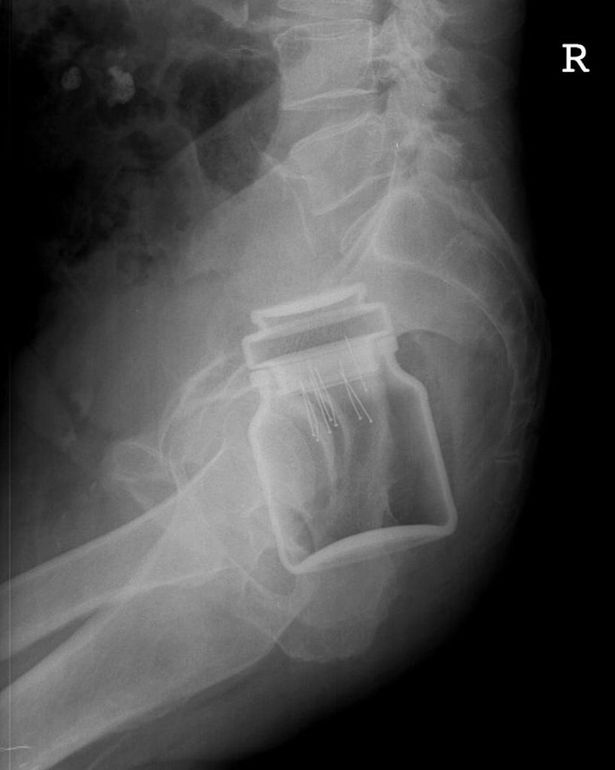

„Iniţial am crezut că glumeşte. La o examinare sumară se putea vedea că este vorba de un corp străin, însă nu am crezut că ar fi chiar un pahar. A fost trimis la o radiografie, iar rezultatul ne-a lăsat mască pe toţi. Era un pahar cu gura în jos”, a spus amuzat un medic din cadrul Unităţii de Primiri Urgenţe, în urmă cu un an.

Cadrele medicale au fost nevoite să îi interneze imediat acesta fiind pregătit pentru o intervenţie chirurgicală. „S-a încercat scoaterea obiectului pe aceeaşi cale, însă a fost imposibil, existând pericolul de a se sparge în interior. Fiind vorba de o zonă puternic vascularizată, era pericolul unei hemoragii masive şi deces.

Borcanul, la fel ca şi paharul de anul trecut, era blocat în zona rectului, astfel că s-a intrat chirurgical şi a fost scos prin abdomen”, a precizat un medic chirurg din cadrul Spitalului Judeţean de Urgenţă „Mavromati”.